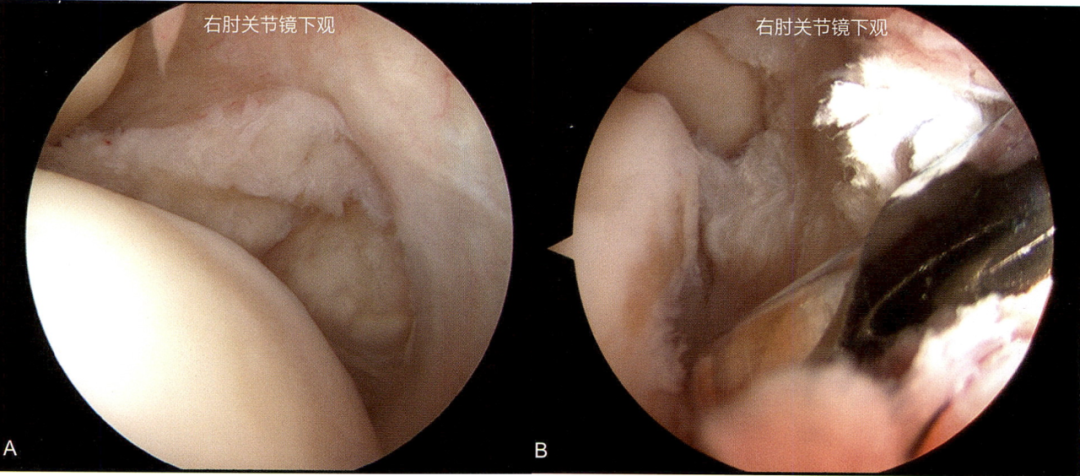

就这样,他被疼痛折磨了两年多,偶尔机会了解到周武忠主任对运动医学疾病的治疗经验丰富,为求进一步治疗,他来到我院找到周主任就诊,结合病史、体查、核磁共振检查,周主任考虑为“顽固性网球肘”,建议通过关节镜微创治疗

微信图片_20250604144937.png

肘关节周围神经血管众多,手术医生要非常有经验,对解剖非常熟悉。术中,周主任在肘关节的两侧,各开了一个仅5mm的微创切口,在镜头的直视下将病灶进行了清理。术后次日,困扰小赵两年多的疼痛明显缓解,“不痛了不痛了!”激动不已。几天后就出院了。目前,小赵的肘关节已经恢复活动自如,再来门诊复查,恢复的不错。